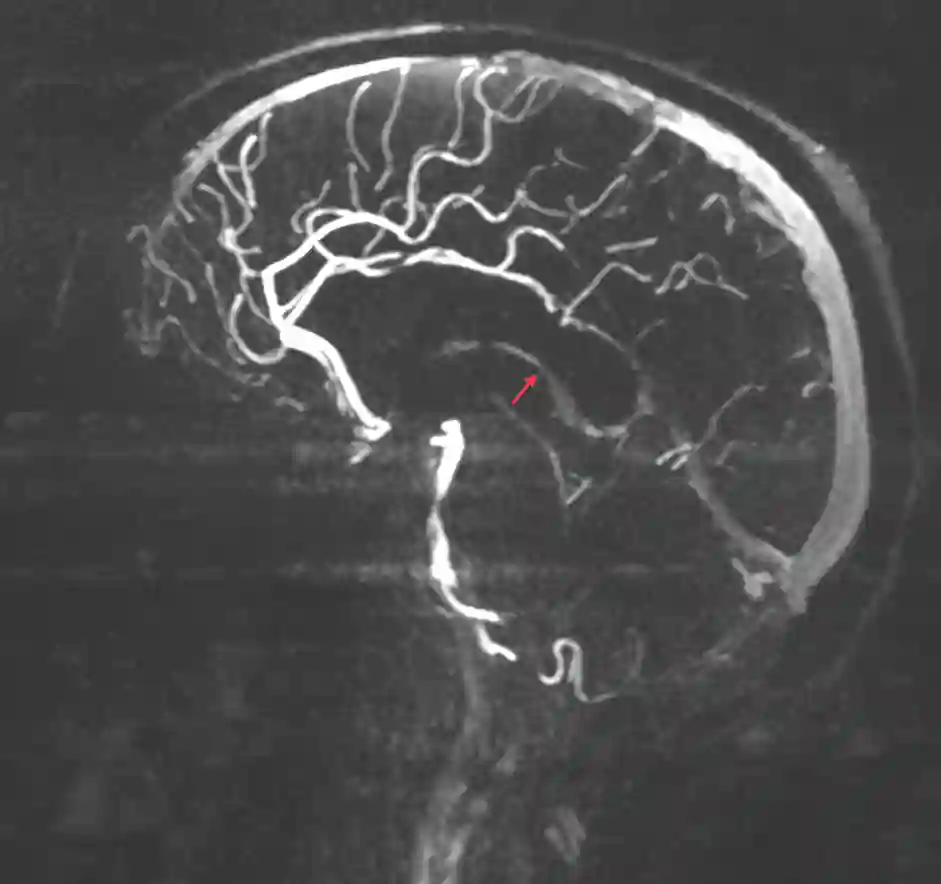

Abbildung

Bildgebung